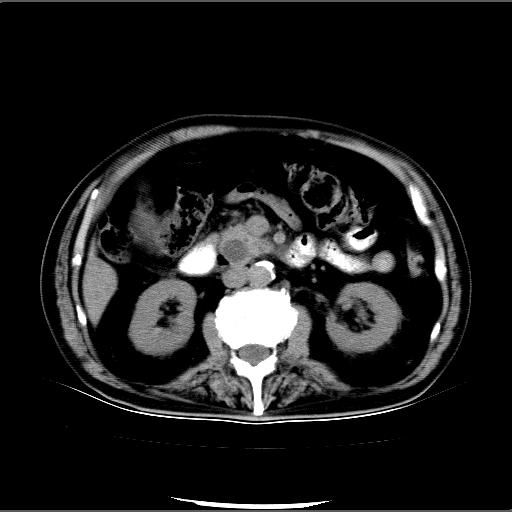

患者男82岁,黄染,发热10天,无腹痛。

1胆总管下端结石伴肝内外胆管扩张;2胆囊颈部结石伴胆囊积液

胆囊多发结石,胆囊积液;胆总管中下段结石,中上段扩张。

1、胆总管壶腹部结石并胆总管、胆囊及肝内胆管扩张。2、胆囊多发结石。3、两下胸膜局限性增厚。4、胃体部大弯侧胃壁稍厚,建议:多量饮水后增强ct扫描除外占位性病变。

胆囊结石、胆总管下端结石,胆囊积液扩大。另外胃壁增厚胃腔缩小,应进一步检查排除皮革胃。

胆囊反折,胆囊结石,胆囊炎,胆总管结石,肝内胆管扩张.

此病例有结果了:患者术后为:胆总管下段结石伴胆道系统扩张;胆囊炎伴胆囊结石。

各位战友分析的都很正确,是一个典型的病例。